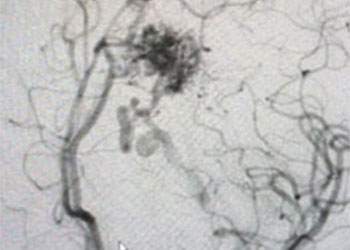

Educational Goals: Learners will be able to recognize the symptoms that may suggest Brain Arteriovenous Malformations, and order appropriate tests to confirm the diagnosis, and refer […]

On admission, she presented as a GCS 3, was intubated, and stabilized hemodynamically in preparation for emergent catheter cerebral angiography, which revealed 2 discrete geographically located […]